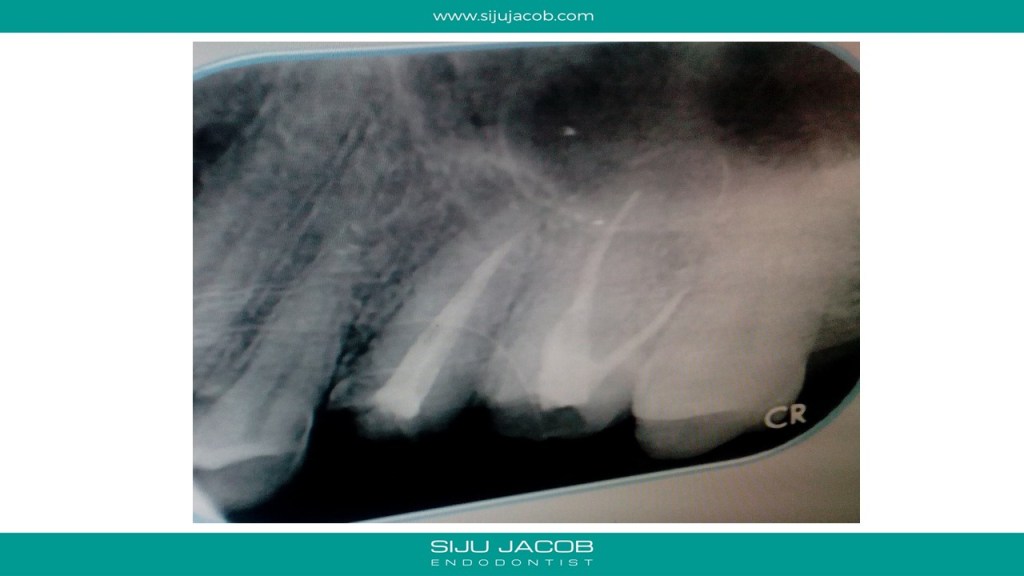

I told her to come and see me for a consultation. I didn’t hear from her for a month. After a month, i received another mail saying that the dentist who did the earlier Root canals had offered to re-do both the root canals and she had gone ahead. She said that she still had discomfort in both teeth. She sent me these images.